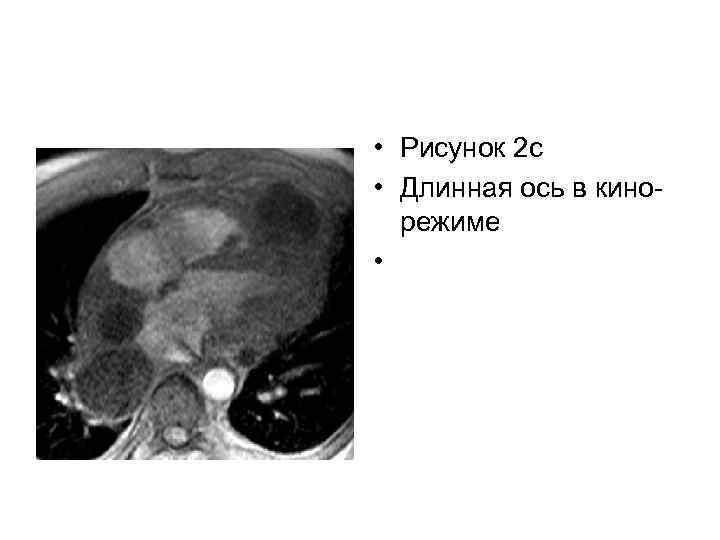

• Рисунок 2 c • Длинная ось в кинорежиме •